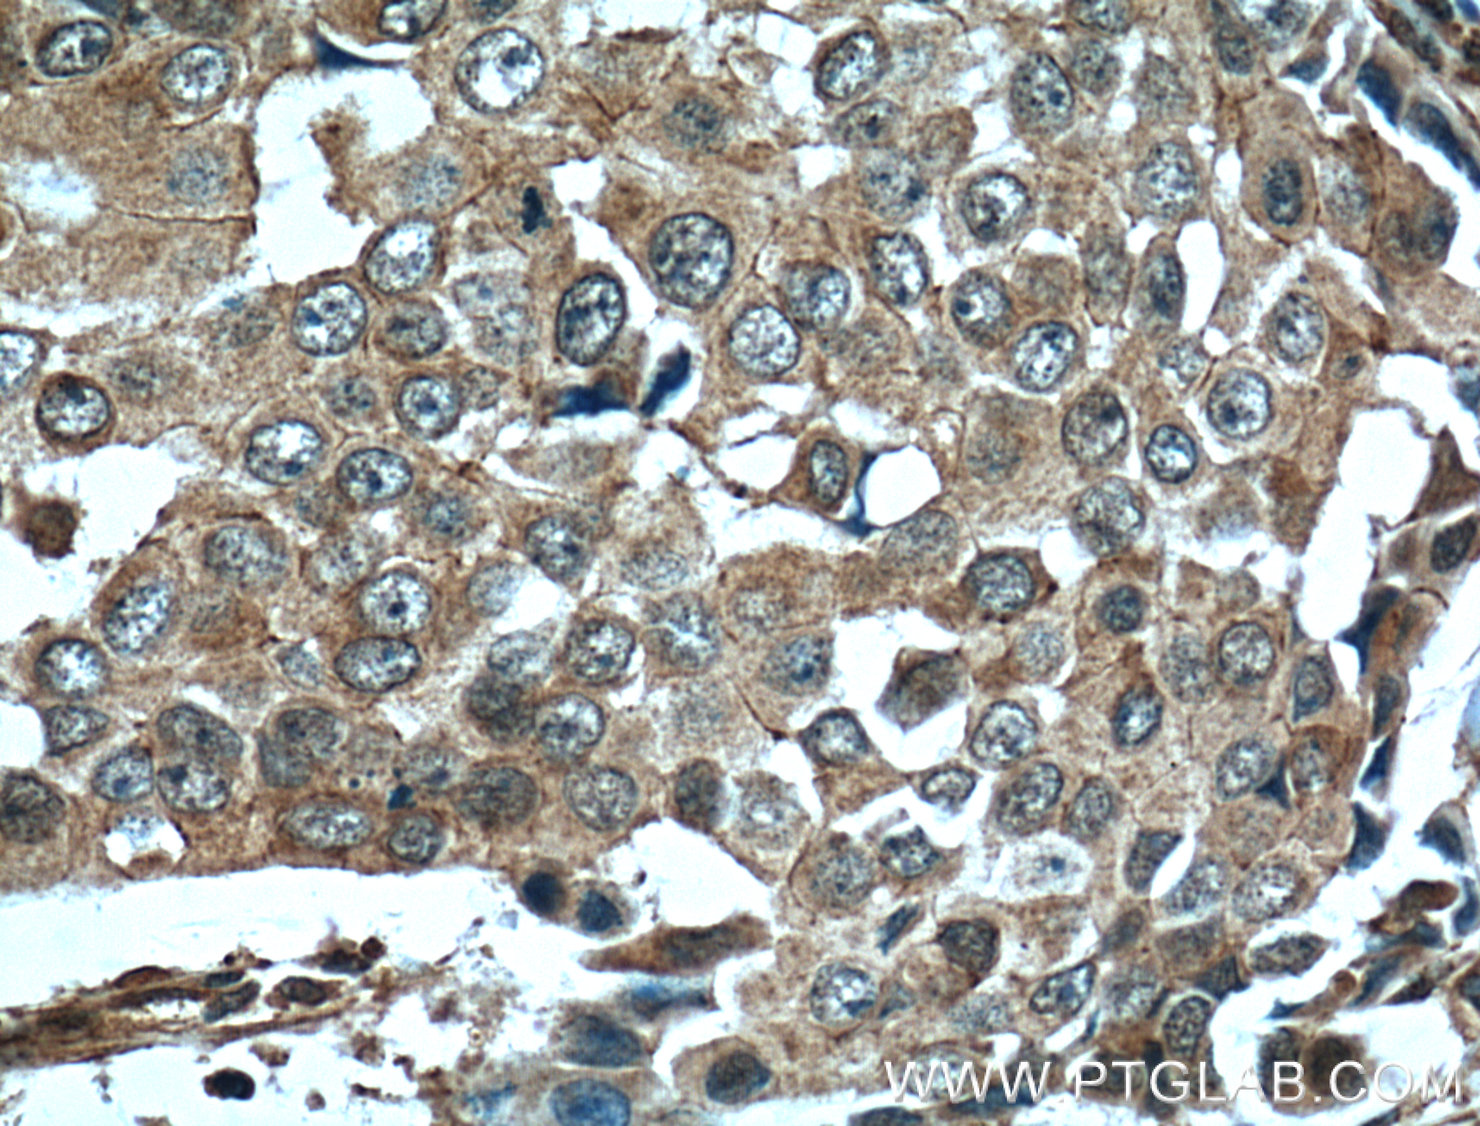

| Positive IHC detected in | human breast cancer tissue, human liver cancer tissue, human stomach cancer tissue Note: suggested antigen retrieval with TE buffer pH 9.0; (*) Alternatively, antigen retrieval may be performed with citrate buffer pH 6.0 |

| Immunohistochemistry (IHC) | IHC : 1:50-1:500 |